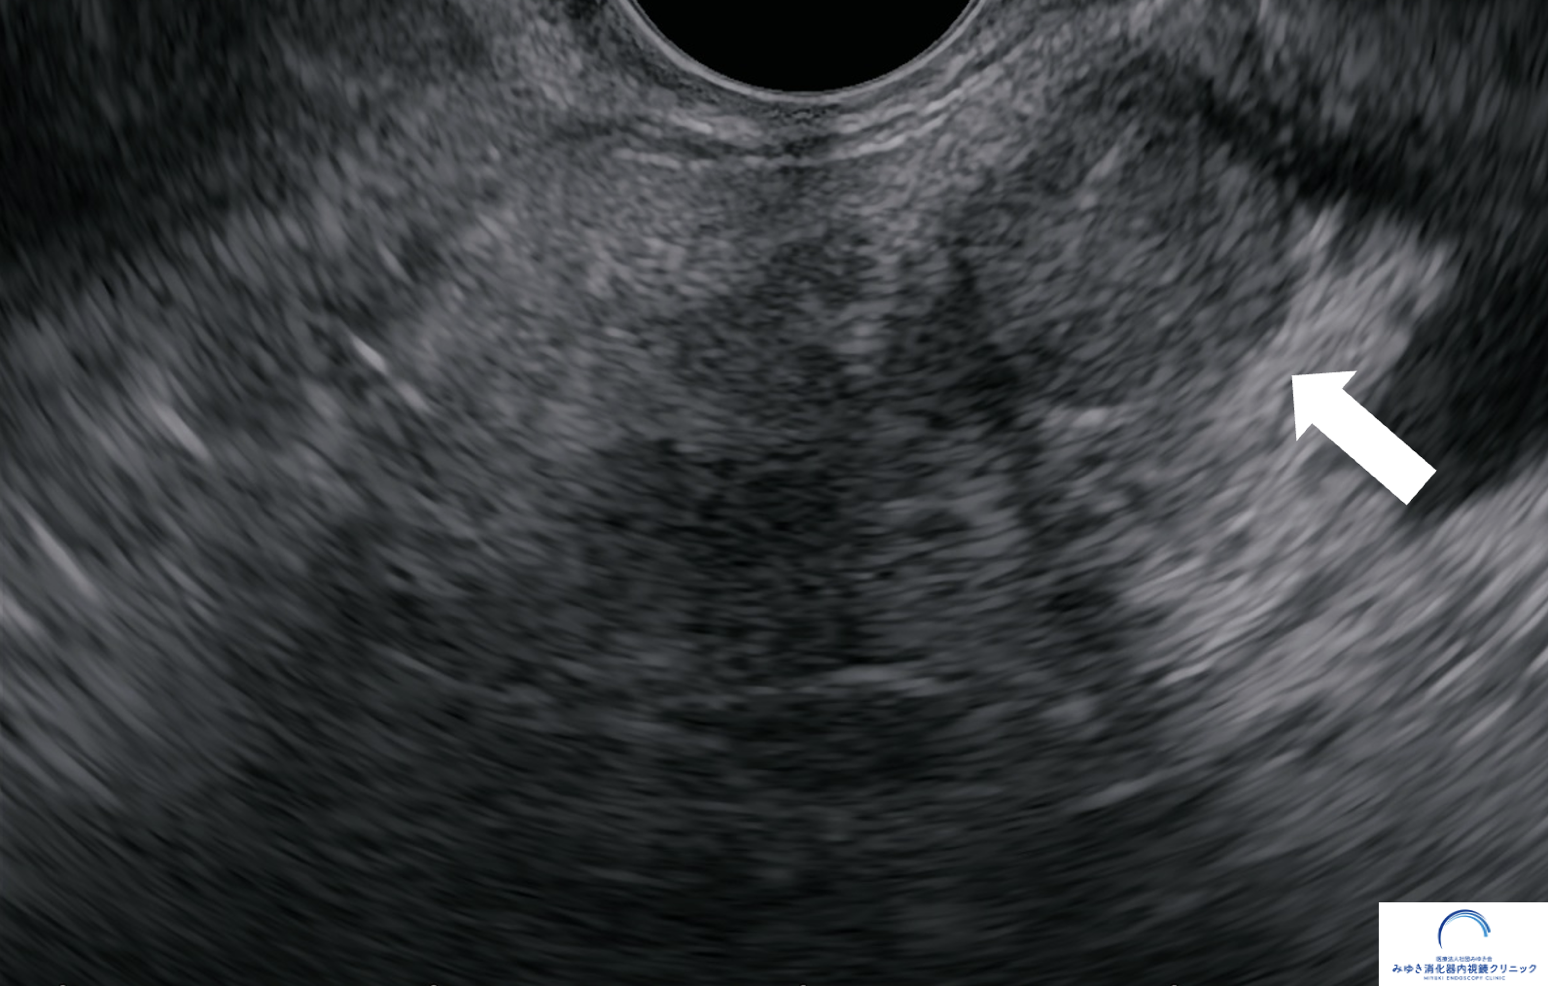

<膵神経内分泌腫瘍>

他院での腹部エコー、CT、MRIでは膵臓に異常を認めませんでしたが、当院での超音波内視鏡検査で10mmの腫瘤を認めました。超音波内視鏡せん刺吸引法(EUS-FNA)で神経内分泌腫瘍と診断しました。